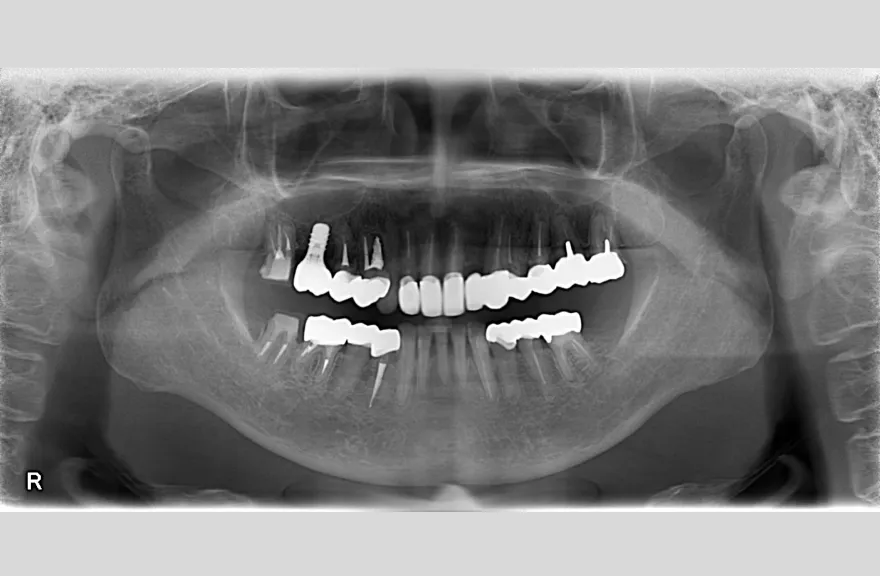

骨格の前後的な差がある方でした。術前のレントゲンより、上下で歯牙の損傷に明らかな差があるのがみてとれます。

既にインプラント治療がなされており、使えるインプラントを使いながら足りないところにインプラントフィクスチャーを埋入し、噛み合わせを再構築する必要がある方でした。

上の前歯、右上の奥歯のインプラントはもう既に使える状態ではなく、また年月を経てすり減ってしまった下の前歯は噛み合わせを再構築する上で利用が難しい状況でした。

年齢を考えると、今回の治療で歯科治療を終えてしまい、残りの人生においてはメンテナンスのみで歯科へ通う状況を作りきってしまうことが求められました。

以上より、潔く残っている歯牙は抜去させていただき、上下をインプラントフィクスチャーによって固定式の歯を入れることとしました。 - 治療のリスク

レントゲンをよく見るとお分かりいただけるかと思いますが右下の奥歯のインプラント(レントゲンでは左右逆にうつるので、左下)が既にインプラント周囲炎になっていました。

本当に治療をやり切ってしまうなら、右下の奥2本のインプラントを抜去、新しいインプラントフィクスチャーを埋入すべき症例でした。

しかし、患者さんとの話し合いで、「まだ使えるインプラントは置いておこう」ということになり、右下のインプラントは置いたまま治療を行っています。今後の人生の中で腫れたり痛む可能性があることは重々ご承知いただいております。

複数のインプラントフィクスチャーの埋入においては埋入位置がずれると後々のクラウン製作に難が生じます。そのリスクを最低限にするため、ガイデッドサージェリーを行っております。